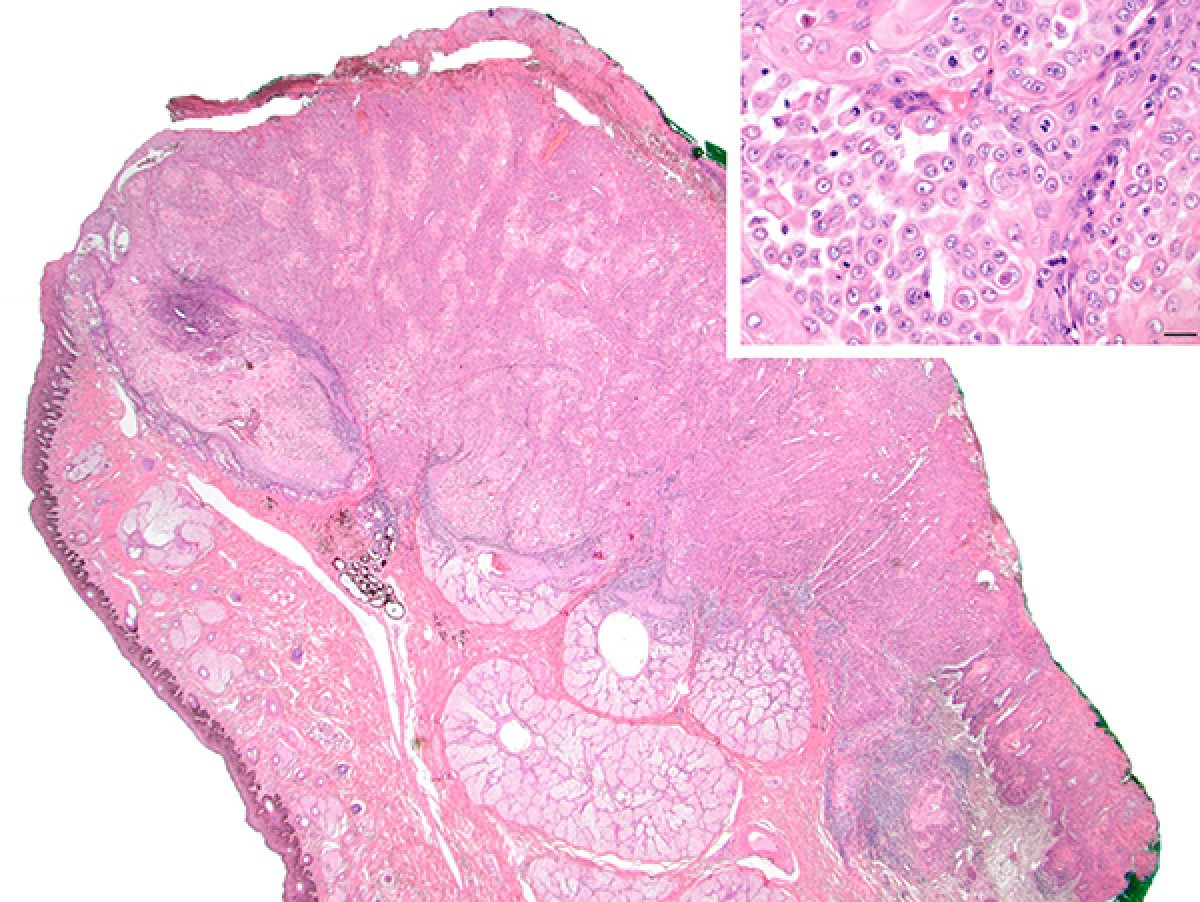

A new study, led by researchers from the Royal Veterinary College (RVC), King's College London (KCL), the University of Edinburgh, and the University College London (UCL), has made a significant advance in the understanding of squamous cell carcinoma (SCC). ), a type of cancer that frequently occurs in horses.

SCC affects the genitals, the eyes, or the skin around the eyes. Tumors often have a reserve to poor prognosis, and available therapeutic approaches have variable success rates. Unfortunately, euthanasia for welfare reasons is necessary in a significant number of cases.

Before this new research was published, pathologists and researchers Dr. Alejandro Suárez-Bonnet and Professor Simon Priestnall, both from the RVC, had already conducted research showing that equine SCC affects the penis often acquires the ability to degrade the extracellular matrix and become much more biologically aggressive. This is known as the "epithelial to mesenchymal transition."

This new study, recently published in Scientific Reports, results from the use of both "classical" anatomical histopathology assessment and state-of-the-art artificial intelligence to demonstrate a correlation between chronic inflammation and equine papillomavirus infection. And the progression of SCC of the equine penis. Several additional cancer-related signaling molecules used in tumors of this location in human medicine were also studied.